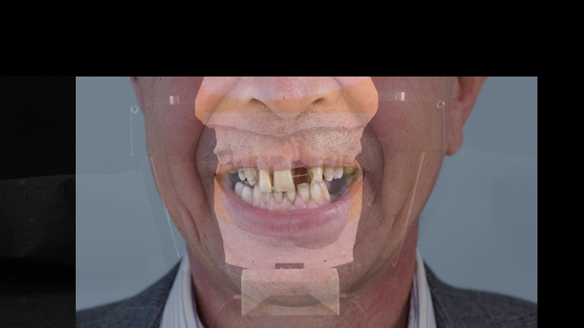

This 52 year old man was referred to me from his general dental practitioner in 2018.

- Generalised periodontitis; stage IV grade C: currently unstable, risk factors: smoker.

- The remaining maxillary teeth had hopeless prognosis in the short term. They exhibited 80 - 100% alveolar bone loss with increased mobility (Grade 2 - 3).

The clinical situation and treatment process is shown in detail below with photographs.